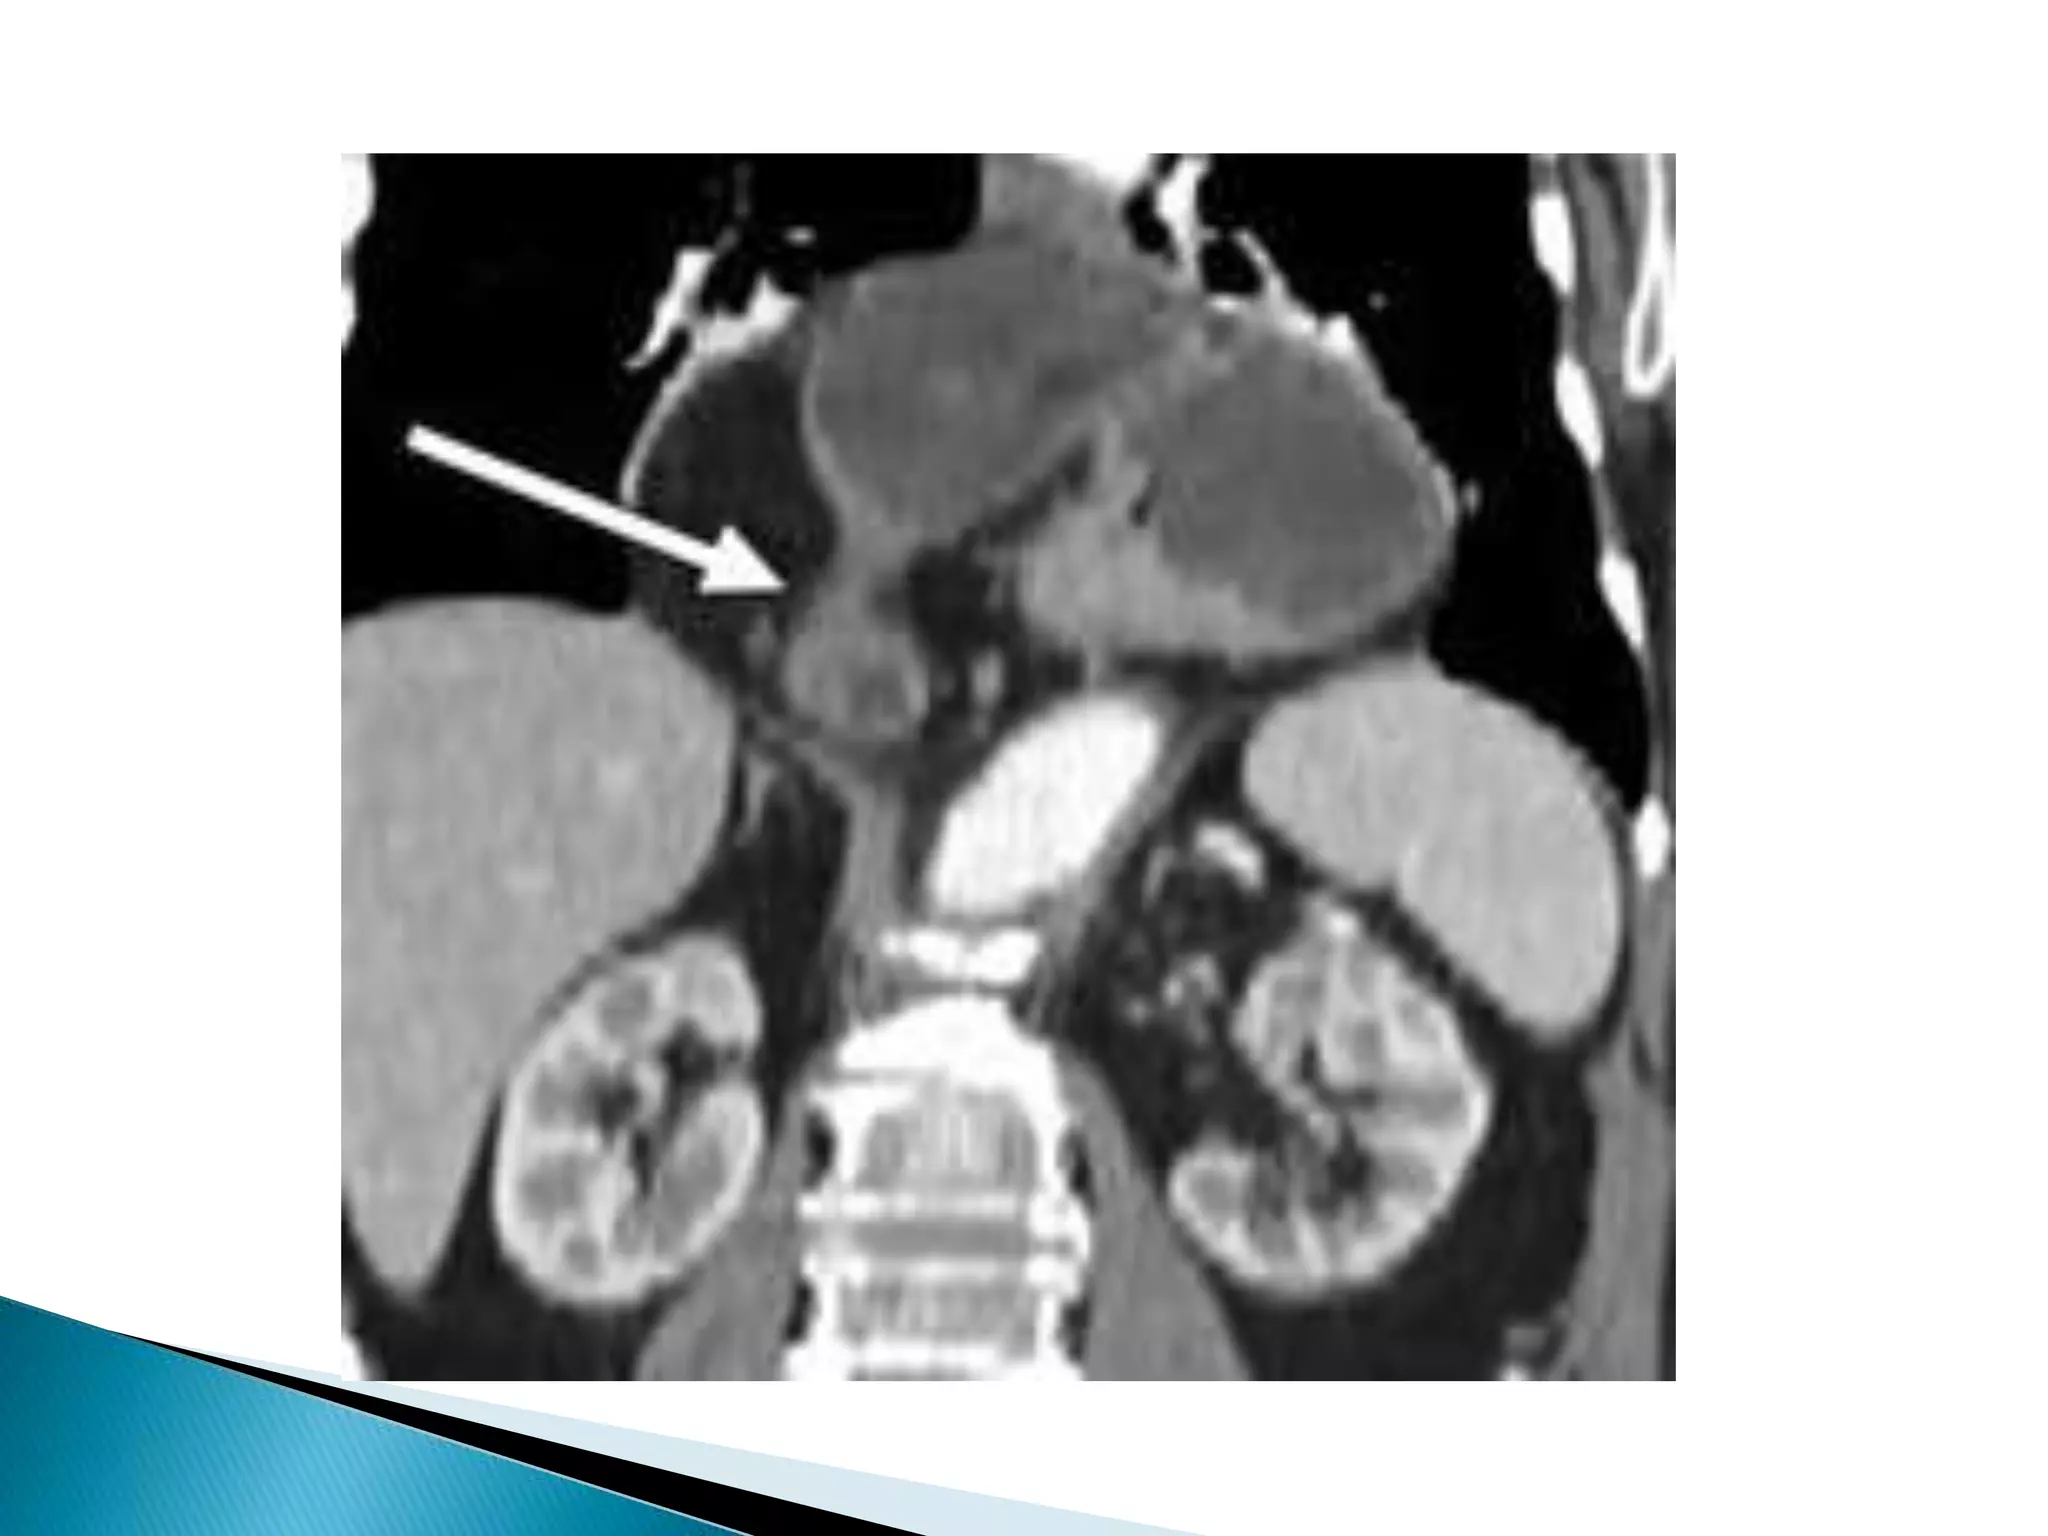

CT findings

 Whirl-like pattern of small bowel loops and

adjacent mesenteric fat converging to the point

of torsion (during volvulus)

 SMV to the left of SMA (NO volvulus)

 "Barber pole sign" = spiraling of SMA